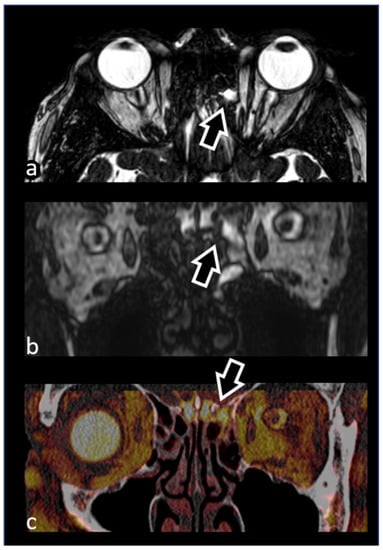

3.1.2. Optic Nerve (II) and Orbital Masses

3.1.3. Ocular Motor Nerves (III–IV–VI)